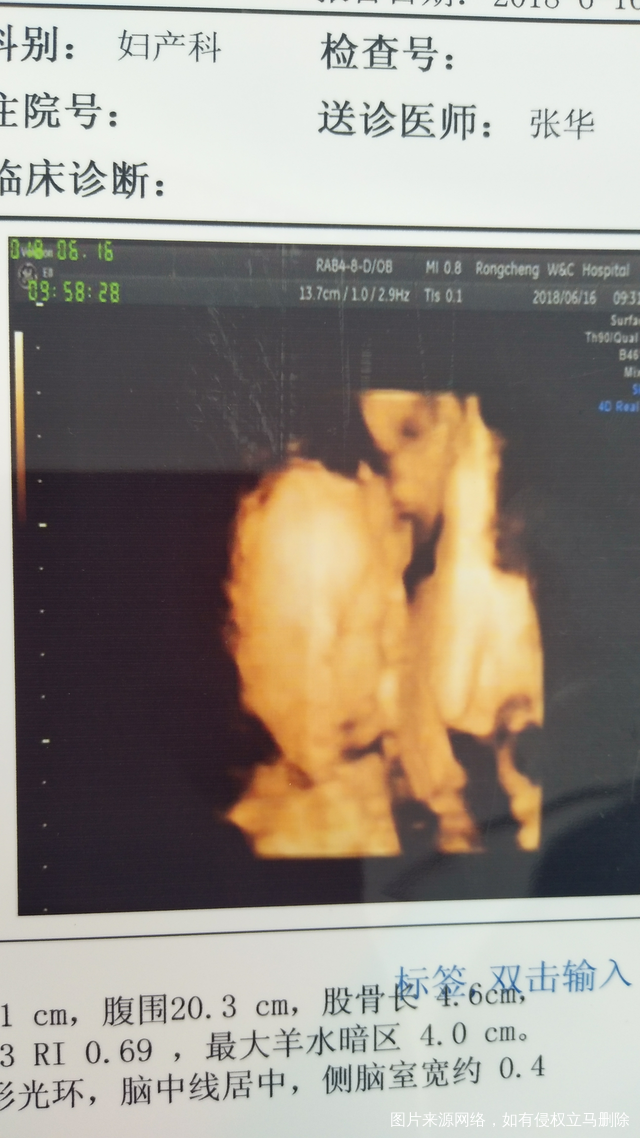

安小慧